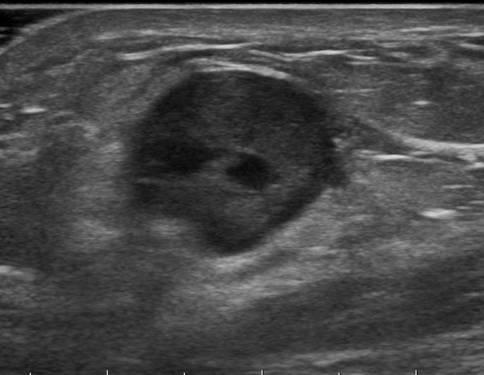

Ung thư vú

» Thông tin: Nữ giới – 54 tuổi.

» Lâm sàng: Khối tuyến vú.